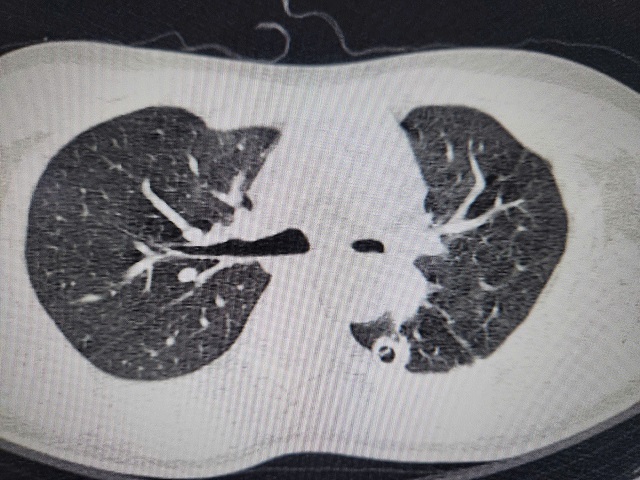

Hình ảnh phim chụp hẹp phế quản gốc trái, xẹp hoàn toàn phổi trái do di chứng của lao phổi

Anh B được chuyển đến Khoa Phẫu thuật Lồng ngực, Bệnh viện Bạch Mai. Qua các thăm khám lâm sàng và chụp chiếu, kết quả quả cho thấy, anh B đối diện với nguy cơ mất phổi vĩnh viễn: Chụp CT 3D phổi cho thấy phế quản gốc trái chỉ còn khe hẹp 2mm, phổi xẹp đặc như tấm bìa cứng. Nếu không phẫu thuật trong 2 tuần, phổi sẽ hoại tử. TS.BS. Ngô Gia Khánh, Trưởng khoa Phẫu thuật Lồng ngực và mạch máu cho biết: Đây là một ca xẹp phổi vô cùng phức tạp với những thách thức lớn. Đoạn phế quản hẹp nằm sâu sau tim, bị che khuất bởi động mạch chủ và động mạch phổi – vùng được mệnh danh là “tam giác tử thần” của lồng ngực. Dù chỉ một nhát cắt lệch 1mm, bệnh nhân có thể tử vong do chảy máu ồ ạt.